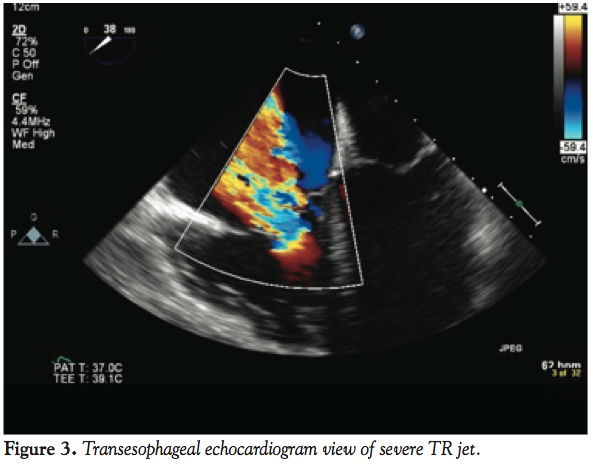

mild shortness of breath. Later that evening, he visited the office of a relative who was a community cardiologist. An EKG demonstrated diminutive R waves in III and aVF, and T-wave inversions in the same leads. There were no ST-T wave segment changes (Figure 1). A transthoracic echocardiogram in the office demonstrated severe tricuspid regurgitation (Figure 2). The patient was directly admitted to the hospital for further cardiac evaluation.

On arrival to the emergency room, vitals were normal; blood pressure was 132/84 and pulse was 63 bpm. A III/VI systolic murmur was noted in the left sternal border. Lungs were clear to auscultation, and the remainder of the exam was normal. The patient underwent a transesophageal echocardiogram (TEE) to evaluate the severity and mechanism of the regurgitant lesion. The TEE revealed moderate right ventricle (RV) dilatation and a distinct akinetic anterior wall of the RV. The severe tricuspid regurgitation was due to tethering of the leaflets, secondary to the underlying wall motion abnormality (Figure 3). The wall motion in other regions was preserved and there were no other accompanying valvular abnormalities.